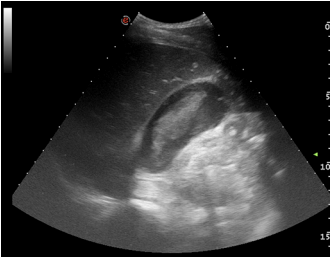

In the course of this imaging, a thin anechoic strip was noticed around the gallbladder

This pericholecystic fluid collection rapidly increased in size on serial FAST examination after 5 min.